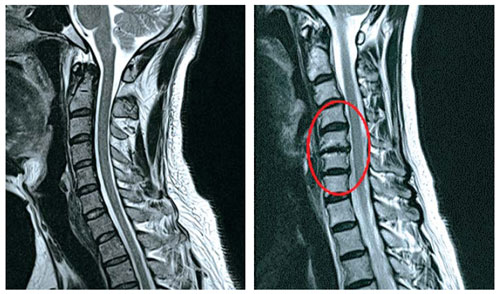

목디스크란?

목디스크는 경추 뼈 사이에 있는 디스크가 돌출되어 신경에 자극을 주게되어 통증을 유발시키는데요.통증이 나타나게 되면 목부터 어깨, 등, 팔이 저리는 현상이 발생을 하며 증상이 안 좋은쪽으로 심화되면 목을 움직일 수 없을 정도로 마비 증상이 올 수 있어요. 디스크의 경우 노화가 진행되면서 풍부하게 일어나지만 사고를 당한 경우 혹은 외부로 부터 충격 또는 잘못된 자세로 인해서 증상이 빠르게 나타날 수 있어요.

목디스크는 목의 근육과 인대에 이어 디스크까지 퇴행되어 밀려 나와 통증을 일으키는 척추 질환이라고 합니다. 현대인들에게 특히나 발병률이 높은데 가장 큰 원인은 스마트폰 사용이라고 합니다.